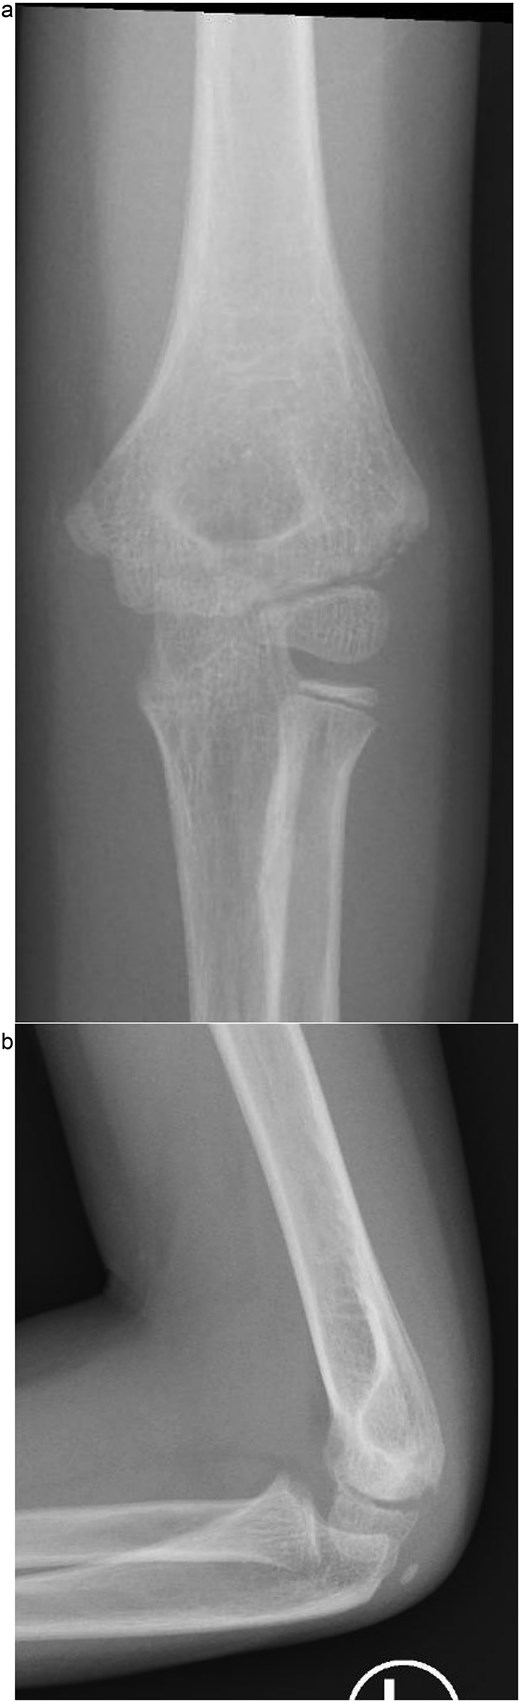

Under procedural sedation, closed reduction of the elbow dislocation was performed, restoring joint alignment and stability. However, post-reduction imaging showed persistent displacement of the lateral condyle fragment (Fig. 2a). The patient was subsequently taken to the operating room, where closed reduction of the condylar fracture was carried out under general anesthesia. As post-reduction displacement was less than 2–4 mm with intact articular cartilage, fixation was performed using two smooth Kirschner wires under fluoroscopic guidance. An arthrogram confirmed joint congruity and cartilage integrity (Fig. 3a). A long-arm posterior slab was applied with the elbow in <90° of flexion to minimize the risk of compartment syndrome (Fig. 4a).

(a) Intraoperative fluoroscopic image following closed reduction and K-wire fixation showing anatomical alignment of the lateral condyle. (b) Arthrogram confirming a congruent articular surface and stable fixation of the fracture fragment.

(a) Postoperative anteroposterior radiograph demonstrating stable fixation of the lateral condyle with two smooth Kirschner wires. (b) Lateral view showing proper wire placement and a well-aligned elbow maintained in a posterior slab splint.